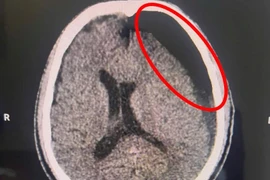

Ngã xe “tưởng nhẹ”, sau 2 tháng mới đau đầu, hôn mê

Kết quả chẩn đoán cho thấy người bệnh bị tụ máu dưới màng cứng bán cấp, tình trạng nguy hiểm có thể dẫn tới tử vong nếu không được can thiệp kịp thời.